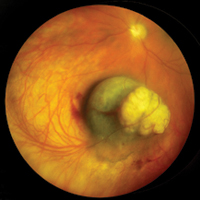

Ocular OncologyImage

Jack A. Cohen, MD

Associate Professor and Director, Section of Ocular Oncology

Image

Rush residents have the unique opportunity to evaluate and manage patients who have benign and malignant tumors of the eye and adnexa. The ocular oncology service is under the direction of Jack A. Cohen, MD, the only fellowship trained ocular oncologist in Chicago. Each year, approximately 20 patients are seen with a variety of eye tumors. Dr. Cohen emphasizes preoperative, operative and postoperative management of these patients with the residents. Residents are exposed to the evaluation and follow-up of these patients, including standardized ultrasonography, radiology, MRI and CT scanning, and biomicroscopy. Additionally, experience with various surgical procedures is obtained, including fine needle biopsy, vitreous and conjunctival biopsy, plaque brachytherapy, external beam teletherapy, dosimetry, spray cryotherapy, transpupillary thermotherapy, chemoreduction and cryotherapy. Surgical therapy of orbital and adnexal tumors are coordinated with the Cornea and External Disease, Oculoplastic, and Neuro-Ophthalmology Sections. At the completion of training, residents are proficient in the recognition, management and referral of patients with a variety of ocular tumors.